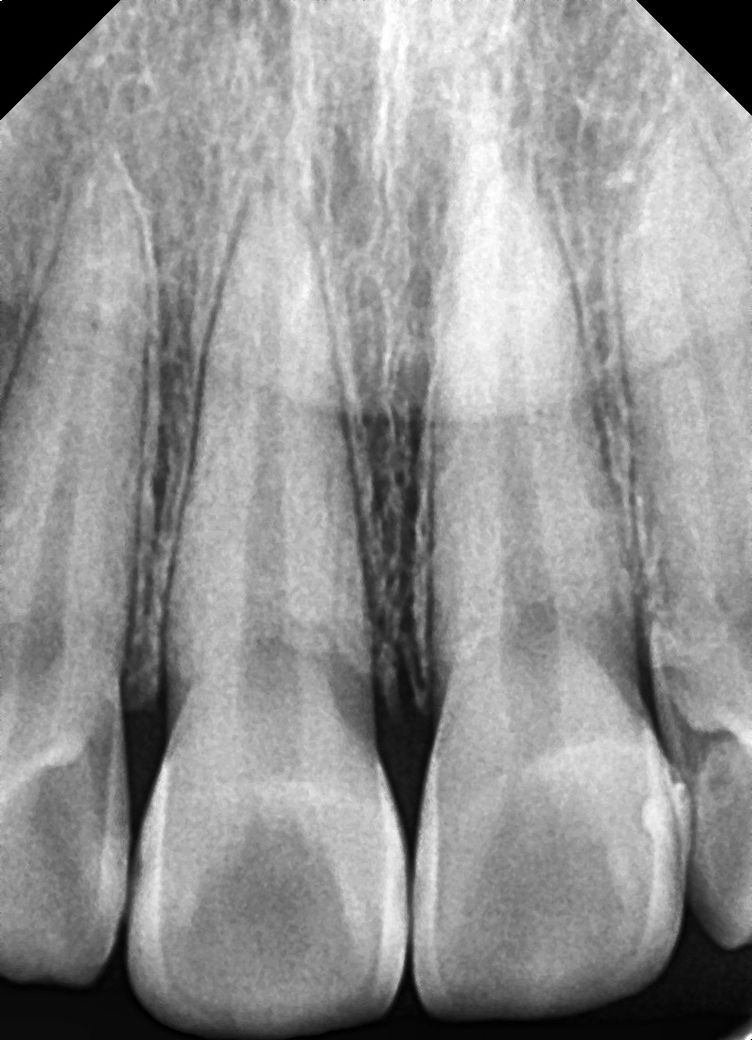

치과 의견이 너무 다릅니다.. 인접면 충치 관련 알려주세요

사진도 제일 많이 찍고 엑스레이사진이 제 주관상 가장 좀 선명?했습니다 인접면 충치가 9개 정도 모인다고 최소 198만원에서 271만원으로 인레인, 레진 치료를 해야한다고 합니다

사진은 a치과 엑스레이 사진입니다!

엑스레이 상으로는 인접면에 충치가 많이 있는걸로 보입니다. 일단 3개월정도 관리를 해보고 그때 가셔서 충치가 진행되면 치료를 진행하시고 관리가 잘되면 계속해서 관리를 해볼것같습니다.

정확한 검사는 따로 해봐야 겠으나 사진상으로는 명확히 충치가 여러군데에서 진행되고 있습니다.

방사선 사진상으로는 작은 충치가 보이긴 하지만 정확한 확인을 위해서는 육안으로 확인을 해야 합니다. 하지만 방사선 사진상으로는 그렇게 큰 충치는 보이지 않습니다.

작은 충치의 경우 관리를 하면 진행이 멈추는 경우도 있습니다.

B 치과 말이 맞습니다. 충치 조금 있는 것은 지켜 보다가 더 진행되면 해도 됩니다. 아마도 A치과는 상담원이 상담했을 가능성도 있습니다.